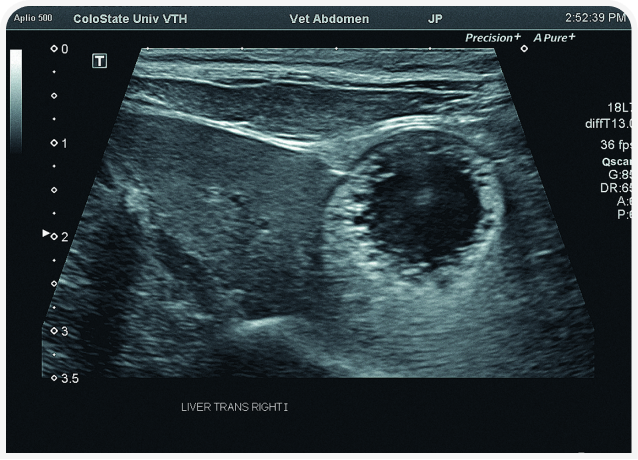

Решающее значение для диагностики и лечения в этом случае будет иметь ультразвуковое исследование органов брюшной полости (Рисунок 6). Диагностику триадита у кошек облегчают визуализация поджелудочной железы и определение толщины/архитектоники стенки кишечника; изменения в паренхиме печени по-прежнему остаются неспецифичными, но изменения в желчном пузыре, скорее всего, помогут установить диагноз. При нейтрофильном холангите у кошки результаты визуализации желчных путей могут оказаться нормальными, но во многих случаях стенка желчного пузыря будет утолщенной и неровной, даже зубчатой (Рисунок 7) (22). Возможны осадок (Рисунок 8) или наличие камней в желчном пузыре, поэтому желчевыводящие пути важно просмотреть до двенадцатиперстной кишки, чтобы исключить внепеченочную окклюзию желчных протоков. Во многих случаях общий желчный проток оказывается перекрыт. Возможен асцит, и в этом случае оправдано проведение аспирации и анализа состава жидкости.

Аспирация содержимого желчного пузыря (чрескожный холецистоцентез под контролем ультразвукового исследования) для цитологического и культурального исследования чаще всего позволяет поставить диагноз и подобрать лечение (Рисунок 9) (23). Если желчный пузырь при визуализации выглядит патологически (например, толщина стенки >1 мм, контур стенки неровный или зубчатый или выраженное гиперэхогенное содержимое (осадок; Рисунок 10), результаты цитологического исследования и бактериального посева, скорее всего, также будут отклоняться от нормы (22,24). Обратите внимание, что при аспирации существует риск разрыва стенки желчного пузыря и/или утечки содержимого с развитием желчного перитонита, но под контролем опытного специалиста УЗИ и при спокойном поведении/седации пациента проблемы возникают редко. Тем не менее если стенка желчного пузыря выглядит эмфизематозной, риск значительно возрастает и вместо аспирации следует рассмотреть возможность хирургического удаления или пробное лечение.